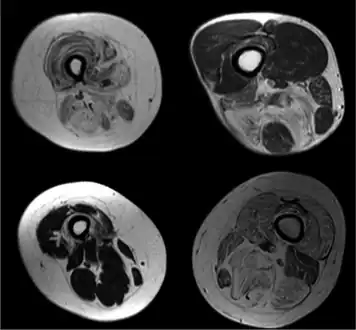

Radiologic imaging in neuromuscular disorders